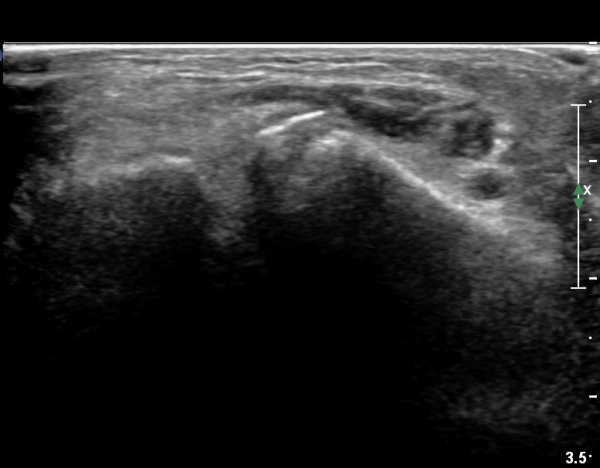

ÃÊÀ½ÆÄ °Ë»ç

she revealed limping gait. on examination, there is swelling around ankle with limited ankle motion, localized tenderness at distal tibiofibular ligament and ATF ligament.